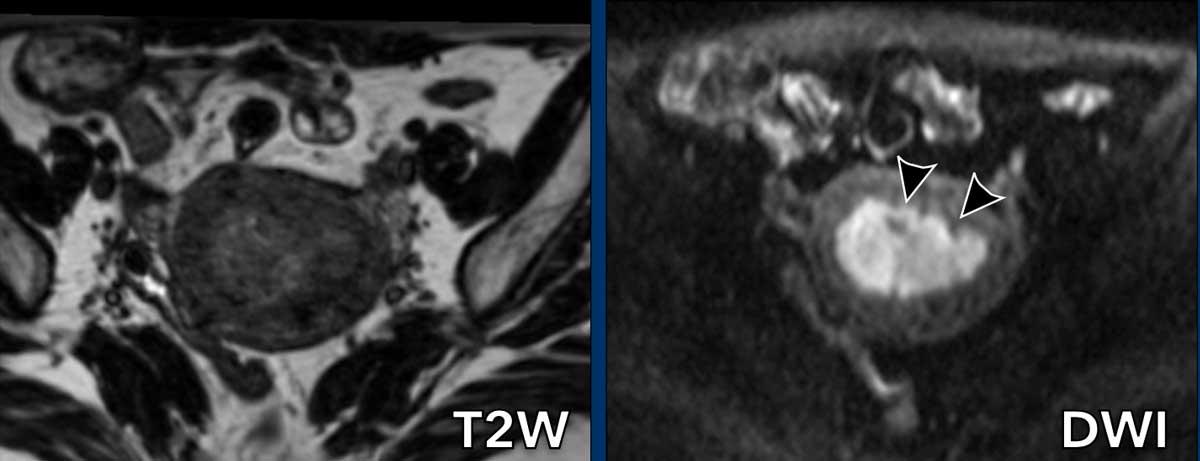

Lợi ích của DWI

Đôi khi khối u khó xác định ranh giới trên chuỗi xung T2W do gần như đồng tín hiệu so với cơ tử cung.

Trong những trường hợp như vậy, DWI giúp phân biệt giữa khối u và cơ tử cung.

Hình ảnh

Trên chuỗi xung T2W, khối u gần như đồng tín hiệu với cơ tử cung.

Chuỗi xung DWI cho thấy có xâm lấn cơ tử cung nhưng dưới 50%.